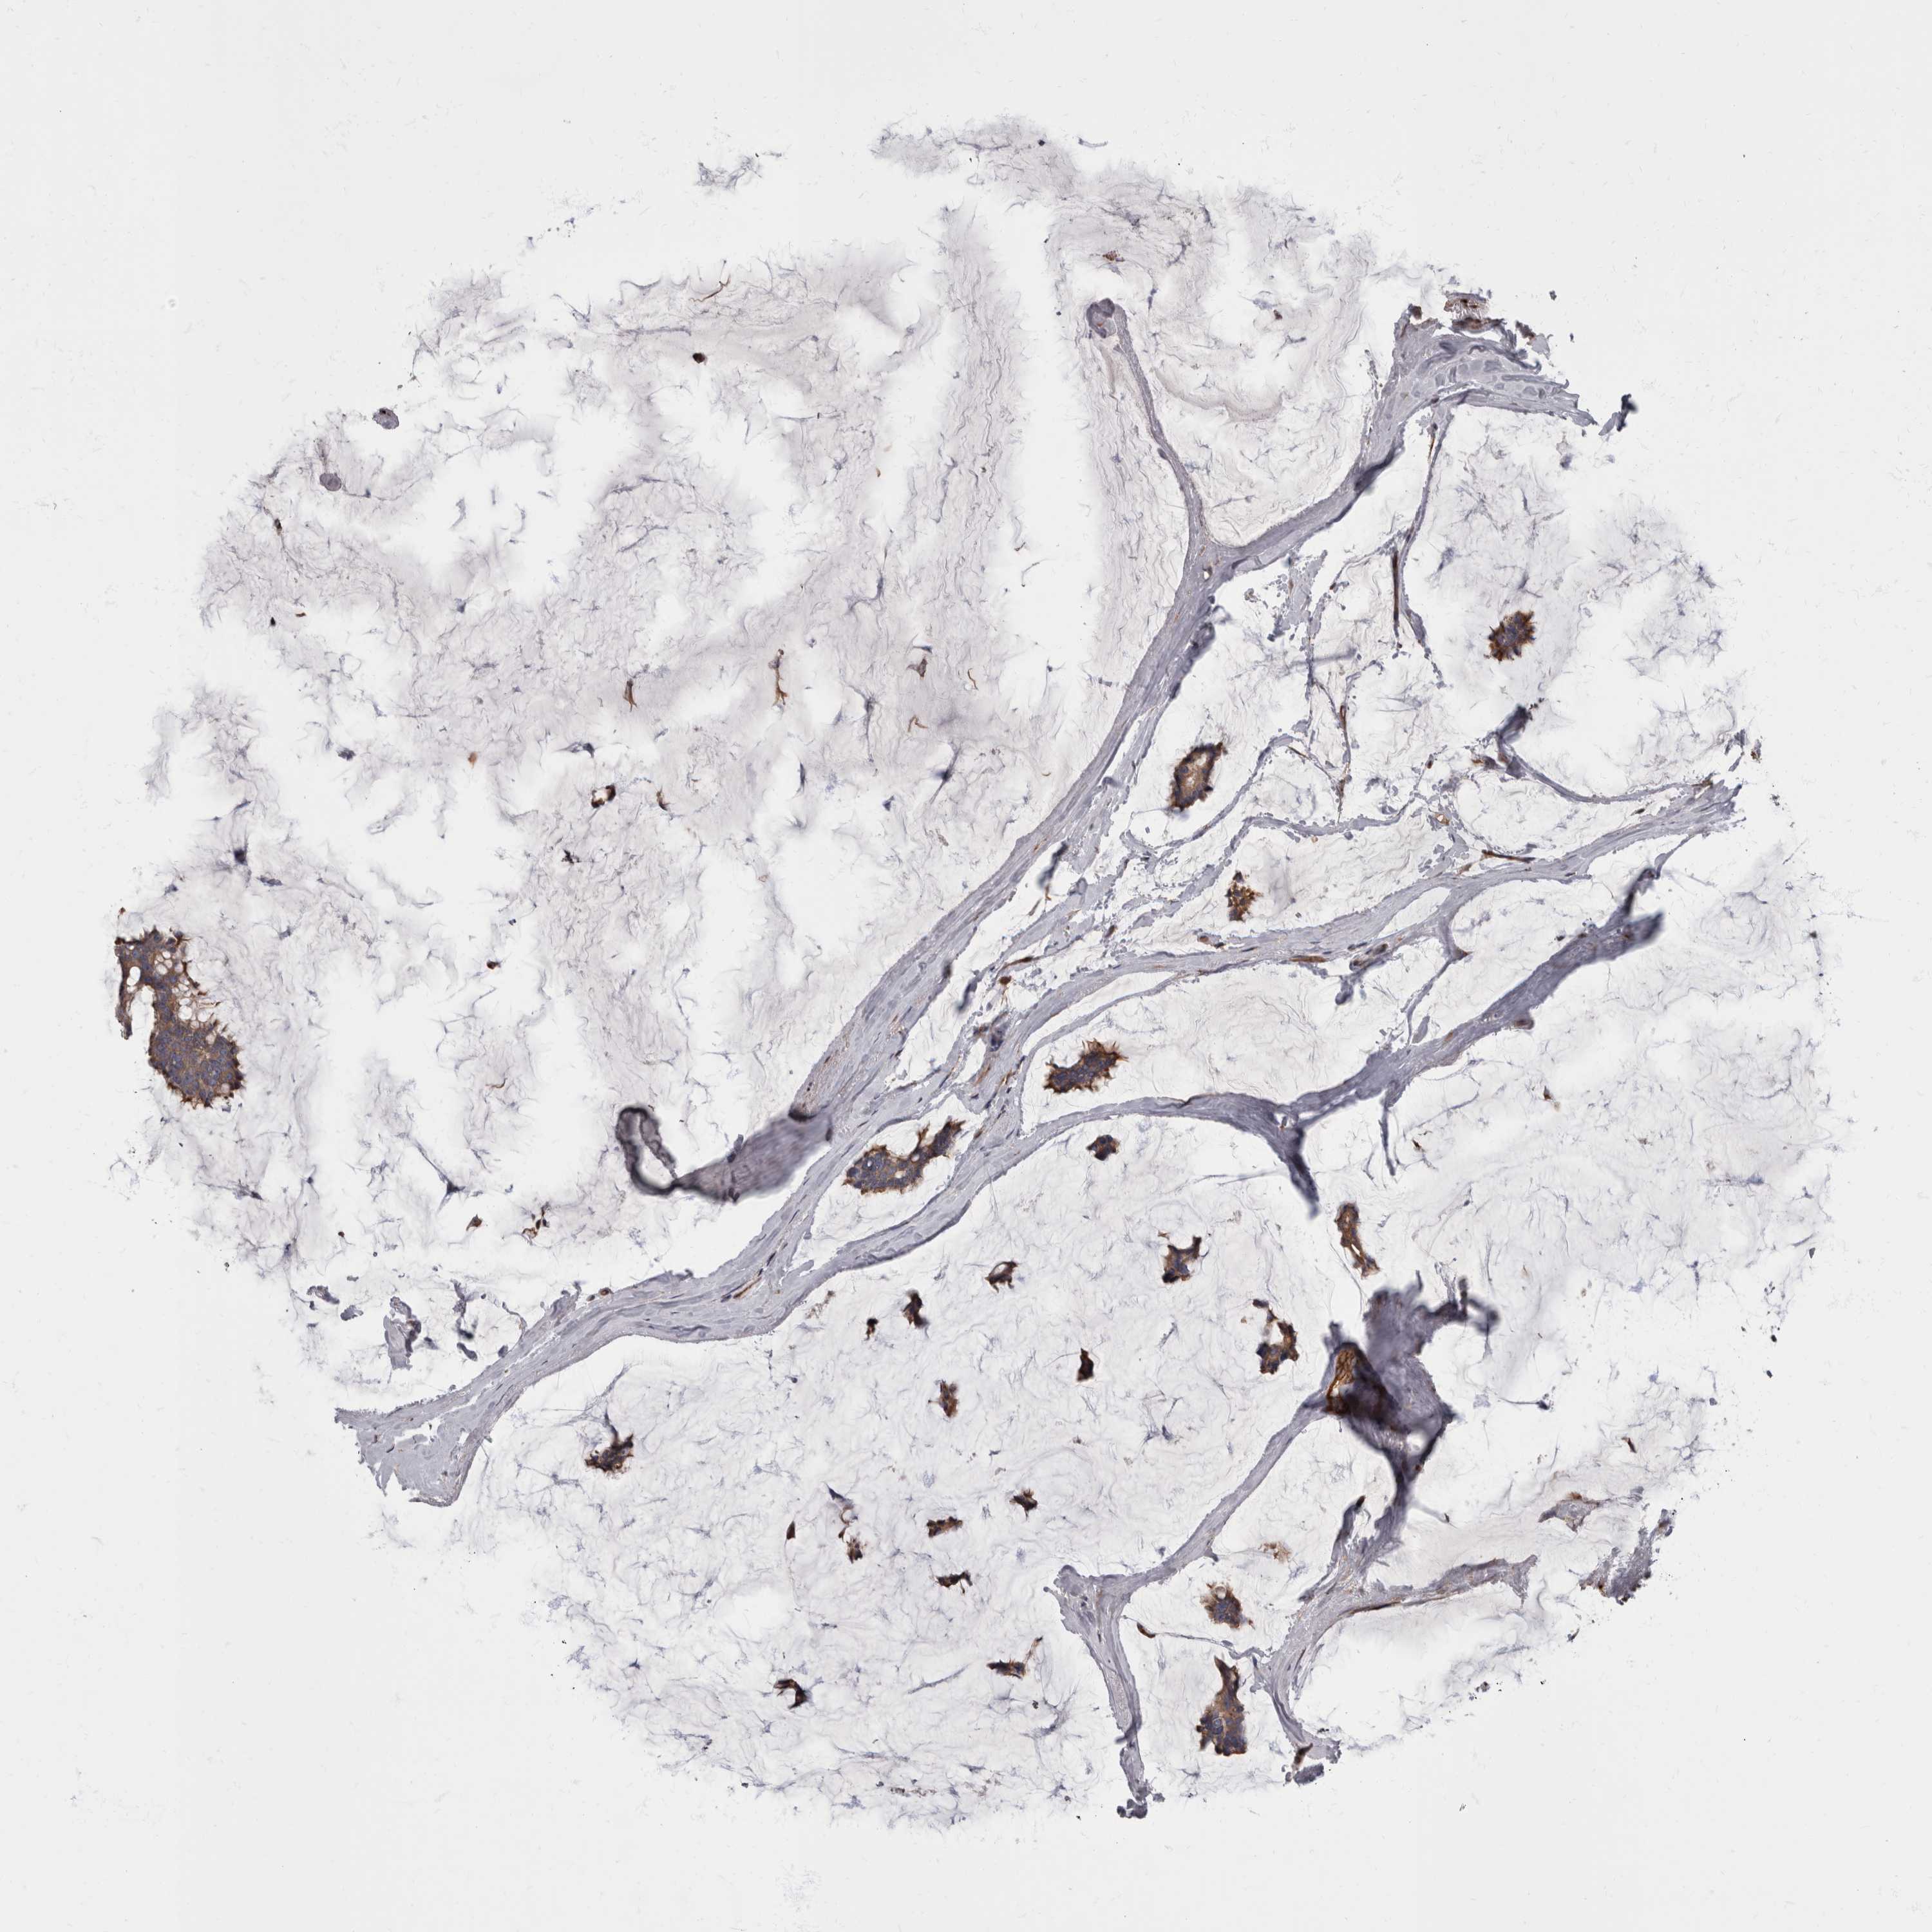

CANCER BREAST CANCER Show tissue menu

BRCA TCGA BRCA VALIDATION PROTEIN EXPRESSION